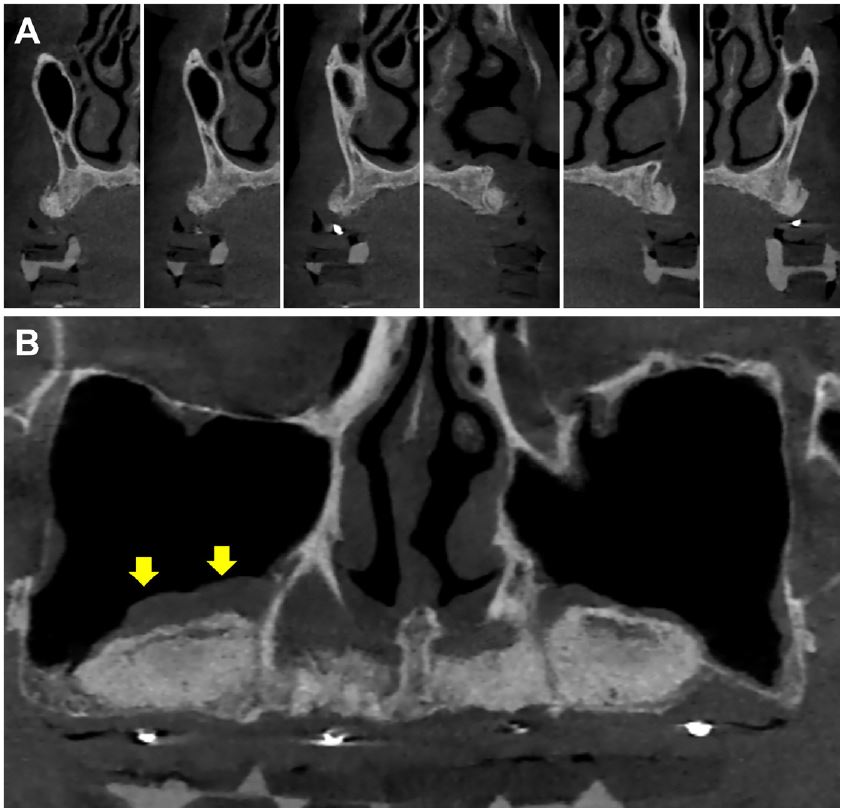

Postoperative CBCT revealed horizontally augmented alveolar bone in the anterior area (Fig. 4A) and vertically augmented maxillary sinus floors following successful elevation with mucosal thickening (Fig. 4B) that was reduced more than that of preoperative CBCT (Fig. 1C).

Fig. 4.

Cone-beam computed tomography (CBCT) view with radiologic guide obtained 5 months after sinus lift. (A) Horizontally augmented alveolar bone ridge in the anterior region, (B) Vertical augmentation in the sinus space is observed. Yellow arrows represent the subsided level of mucosal thickening at the right sinus floor.